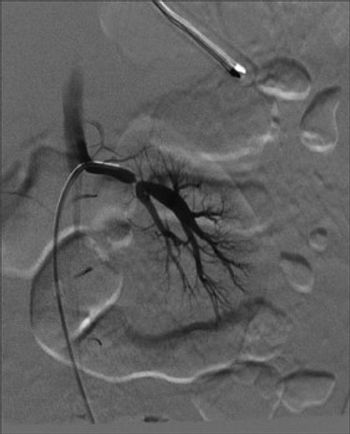

Hypertension and diabetes, hypertension and stroke/dementia, renal artery stenosis and hypertension in children, pulmonary arterial hypertension, portal hypertensive gastropathy, central retinal vein occlusion-a close look at some common hypertension-related conditions.